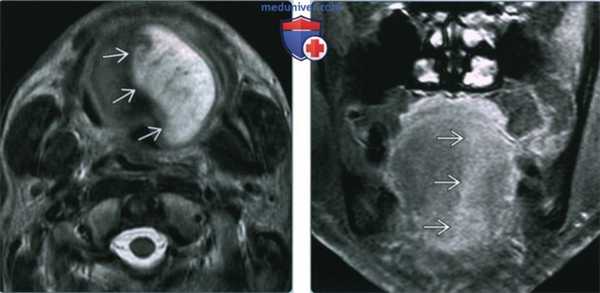

(Слева) МРТ Т2ВИ, аксиальная проекция. Денервация языка в острую стадию. Выраженный отек половины языка с повышением интенсивности сигнала. Обратите внимание на четкую демаркационную линию. Денервация была обусловлена переневральным ростом опухоли вдоль ЧН XII.

(Справа) МРТ Т1ВИ FS с КУ, подострая денервация языка. Накопление контраста в мышцах левой половины языка. Обратите внимание на четкую границу между половинами. Причиной денервации стало метастатическое поражение основания черепа, в том числе подъязычного канала.

3. МРТ при моторной денервации подъязычного нерва:

• Интенсивность сигнала варьирует в зависимости от степени денервации

• Острая стадия (обычно менее одного месяца):

о Язык отечный, дряблый

о Повышение интенсивности на Т2ВИ, незначительное снижение Т1ВИ

о В острую стадию интенсивность накопления контраста вариабельна

• Подострая стадия (обычно 1-20 месяцев):

о Отек разрешается, жировая атрофия

о Гиперинтенсивный сигнал на Т1ВИ, снижение интенсивности контрастирования

• Хроническая стадия (обычно более 20 месяцев):

о Атрофия половины языка

о Выраженный гиперинтенсивный сигнал на Т1ВИ, контраст не накапливается

(Слева) МРТ Т1ВИ. Хроническая атрофия языка с выраженным повышением сигнала от левой его половины, которое характерно для жировой атрофии. Причиной паралича являлась параганглиома яремного отверстия (не показана).

(Справа) КТ с КУ, аксиальная проекция. Жировая атрофия вследствие хронической денервации левой половины языка. Правая половина языка выглядит крупнее левой, ее можно принять за опухоль. Как оказалось, причиной денервации является деструктивная костная опухоль на уровне подъязычного канала.

(Слева) На аксиальной МРТ (Т2 ВИ) в острой фазе денервации языка определяется отек и значительное повышение интенсивности сигнала половины языка вследствие отека. Оцените четкое отграничение патологического участка. Причиной денервации стало периневральное распространение опухоли вдоль ЧМН XII.

(Справа) На корональной МРТ (Т1 ВИ С+ FS) определяется признак подострой денервации - неравномерное контрастирование мышц левой половины языка. Обратите внимание, что изменения, обусловленные вторичным поражением основания черепа с вовлечением подъязычного канала, четко отграничены.

(Слева) На аксиальной МРТ (Т1 ВИ) определяются признаки хронической денервации языка с выраженным повышением интенсивности сигнала в его левой половине, сопоставимые с замещением жировой тканью. Подъязычная денервация может быть обусловлена параганглиомой яремного отверстия (не визуализируется).

(Справа) На аксиальной КТ с КУ определяется жировая атрофия вследствие хронической денервации левою подъязычного нерва. Правая половина языка выглядит больше, чем левая и может быть ошибочно принята за опухоль. Причиной денервации стала деструкция кости в области подъязычного канала.